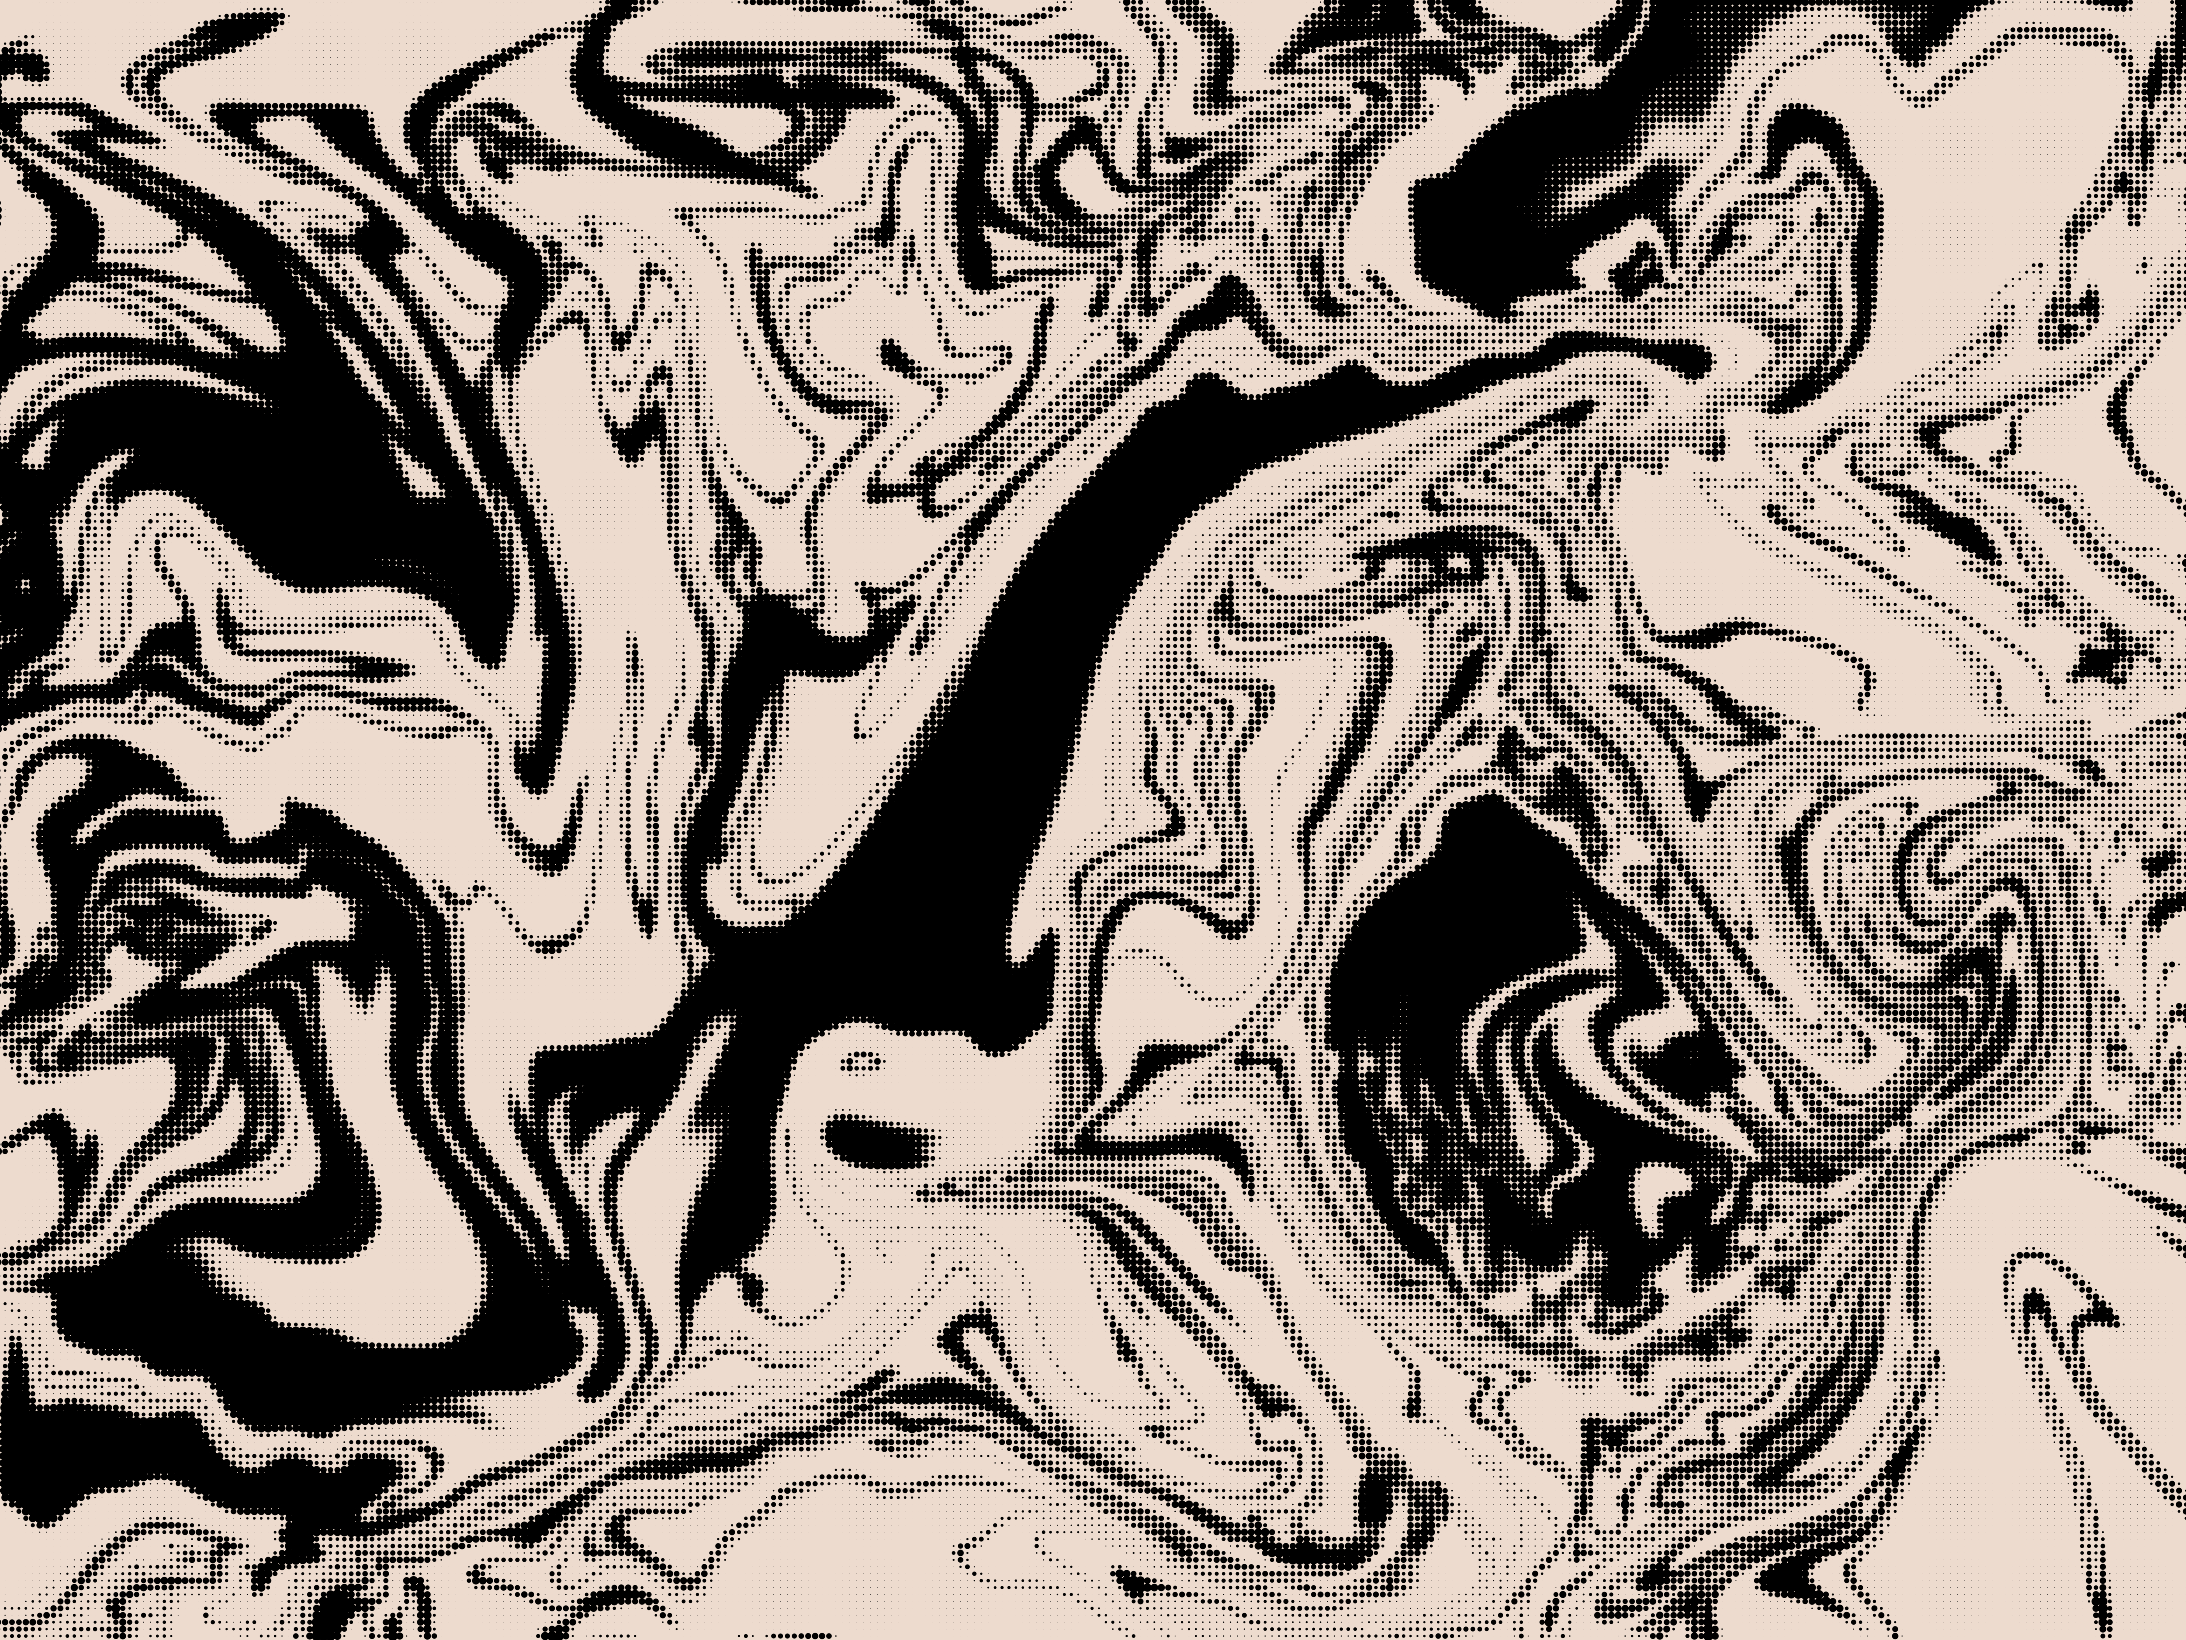

Picto Part II.a (2021)